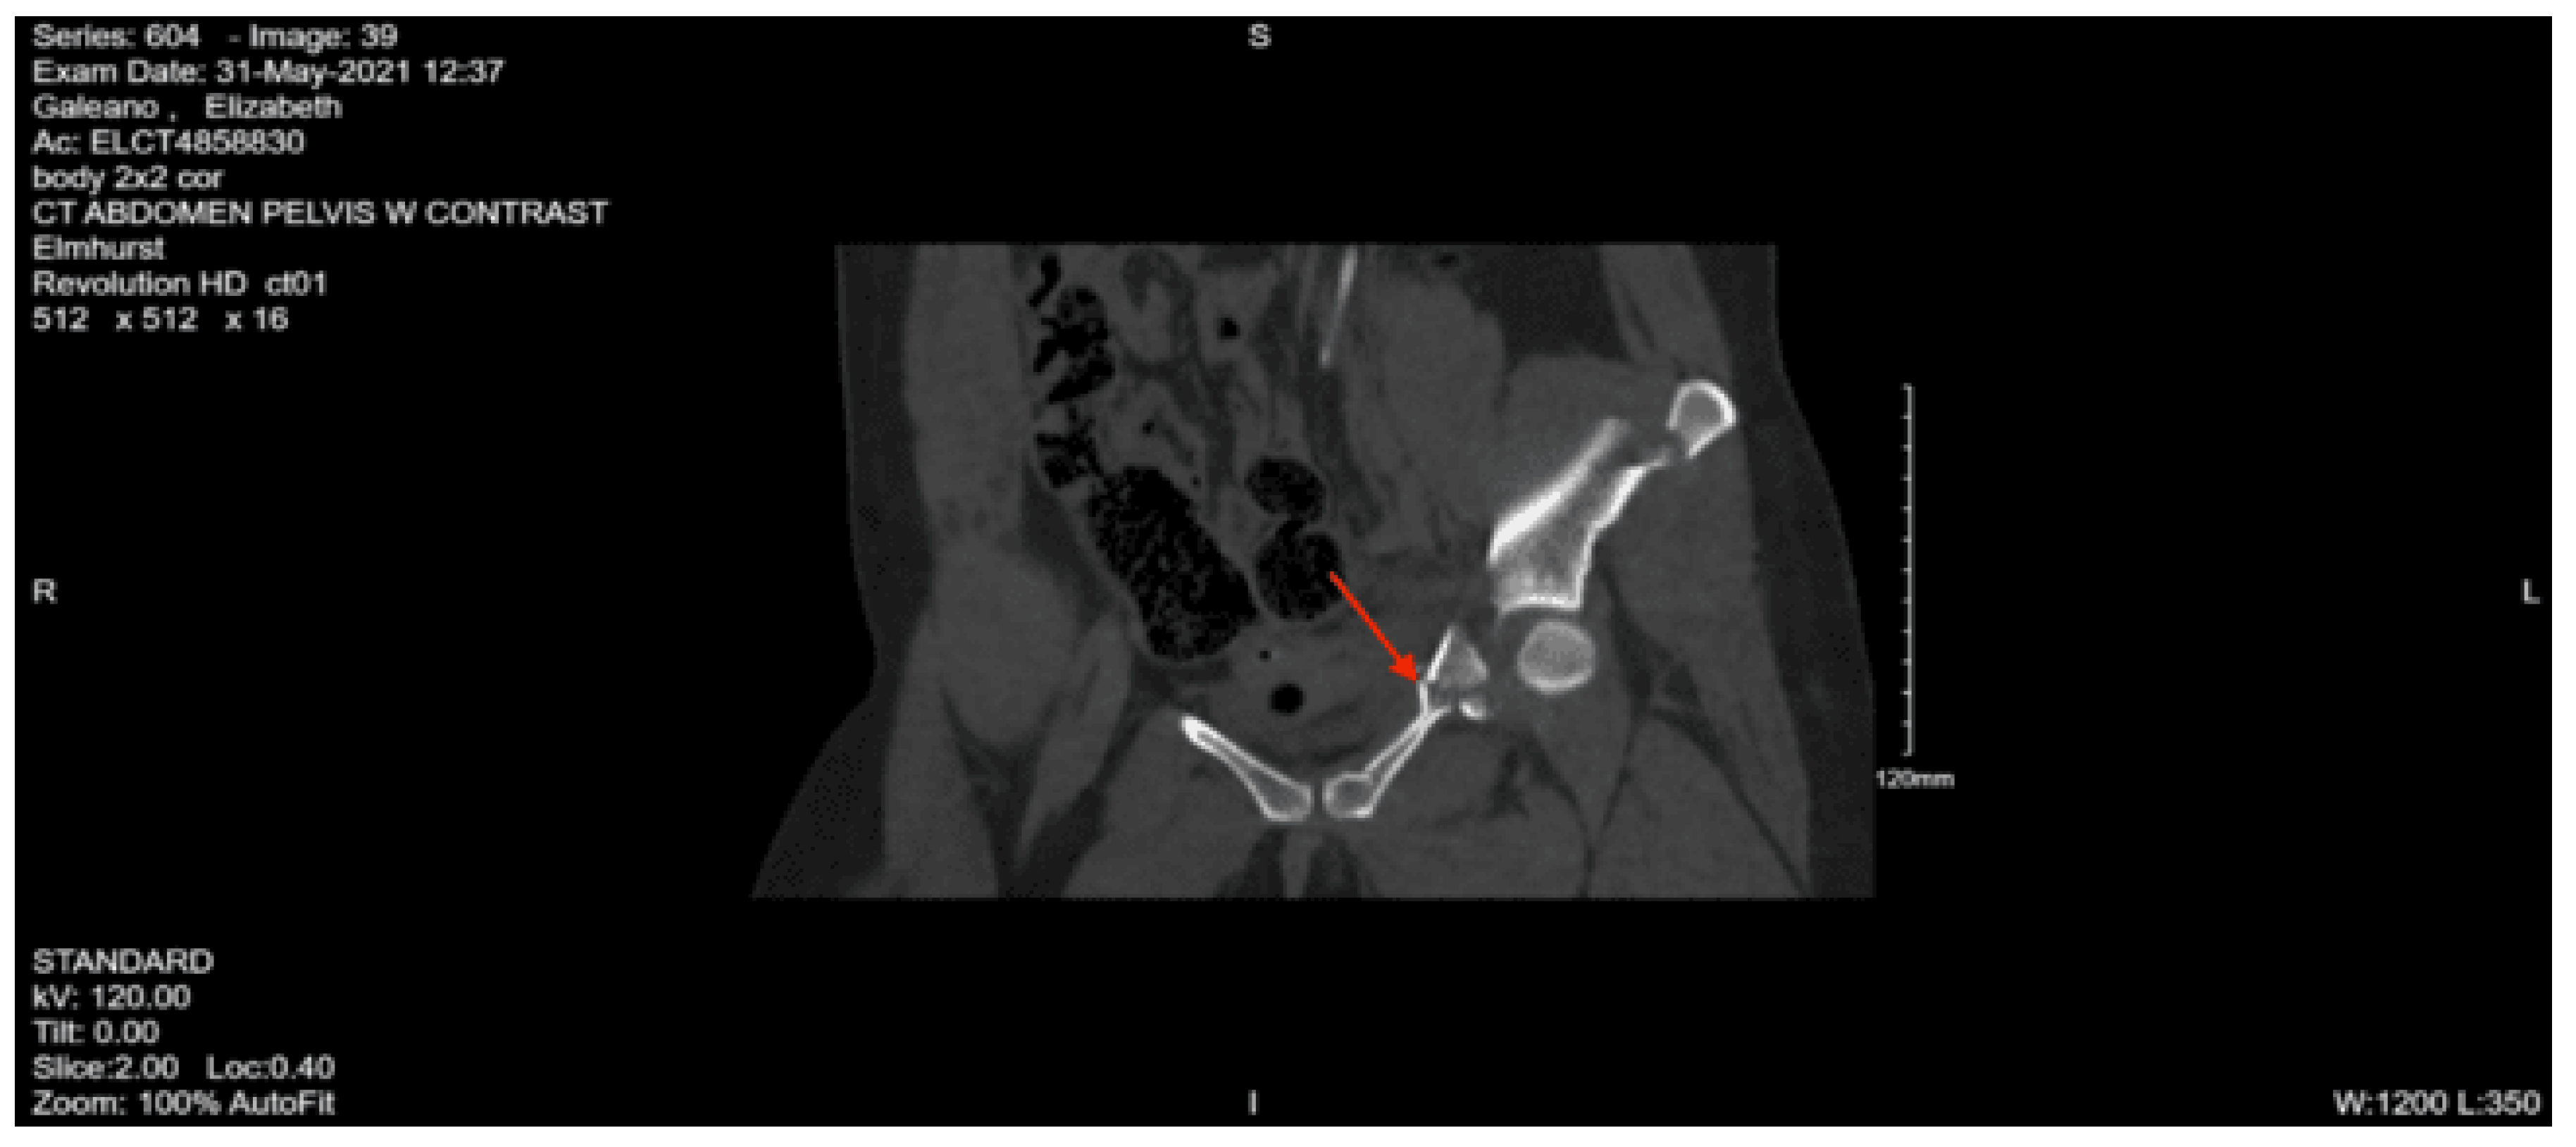

Imaging as shown in Figure 4, Figure 5 and Figure 6:

CT abdomen and pelvis with contrast: No acute visceral traumatic abnormality. There is evidence of an acute impacted fracture involving the left superior and inferior pubic rami. The right superior and inferior pubic rami are intact. The sacrum and coccyx appear unremarkable.